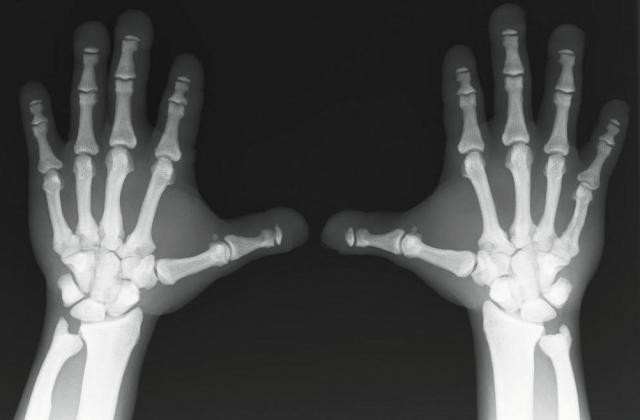

Развивается в результате нарушения кровоснабжения, наличия опухоли или хронической инфекции. Рентгеновский снимок – единственный способ определения заболевания для постановки диагноза. На рентгенограмме пораженные участки кости более темные по сравнению со здоровой костью. При рассмотрении пораженных болезнью костей на снимке они выглядят крепкими, но это впечатление обманчиво. Остеосклероз снижает упругость костей, их качество и механические функции, повышая ломкость.

- Остеопойкилия. Генетическое заболевание скелета, которое сопровождается многочисленными очагами остеосклероза. Никакими симптомами себя не проявляет, обнаруживается после рентгеноскопии.

- Пикнодизостоз. Тяжелое нарушение, выявляется в раннем возрасте. Характерные признаки: дети отстают в физическом развитии, имеют укороченные кисти рук, нарушение строения скелета лица, зубов, развивается системный остеосклероз, имеют место частые патологические переломы.